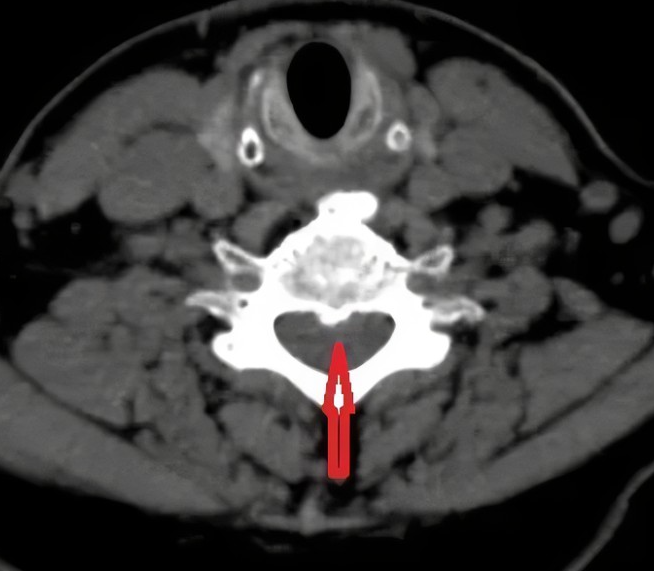

71岁的患者陈大妈,身体一直很好,去年开始肩颈就一直不舒服,起初就有轻微疼痛,最后发病难以承受。遂在家属陪同下至珠海广安手足外科就诊。手外科主治医生谭新德询问患者后了解到:由于长期伏案工作后出现颈后部疼痛,夜间疼痛加重,休息后好转,每天早晨起床时出现颈部僵硬,活动约半小时后缓解,疼痛加重时口服止痛药,外用膏药后,疼痛略缓解。

因患者自觉颈部酸胀疼痛加重,疼痛反射至右侧肩部、右侧上肢至手腕部,不能正常持物,夜间多次被痛醒,影响睡眠。床上翻身时,头身不能正常协调完成翻身动作,严重影响日常生活,要求保守诊治,拟“颈椎病”收住入院。